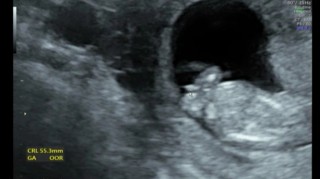

母子手帳を貰ってから初めての妊婦健診でした(*Ü*) 相変わらずつわりが酷くて、特に夕方〜夜は吐き気と頭痛がピークで動けません(><)(´;_;`) 赤ちゃんはちょうど起きてたみたいで元気いっぱいに動きまくってました! BPD2cm、CRL4.9cmでした(*ˊᵕˋ*) 次は4週間後!性別わかるかな〜(っ ॑꒳ ॑c)✩

寝てるみたいです♡大きさは6.45センチくらいでした!